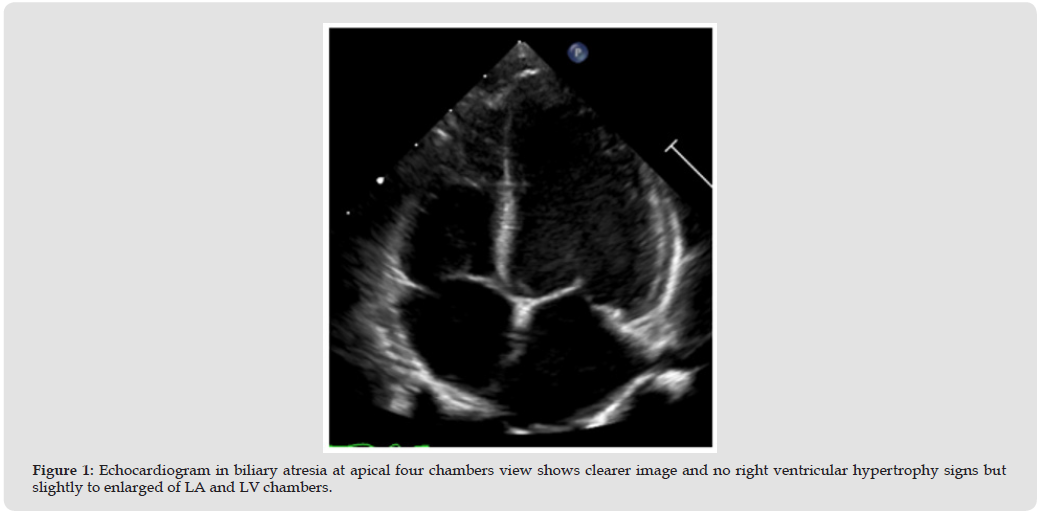

Alagille syndrome have main condition associate with cardiac are right side heart obstruction such as peripheral pulmonary artery stenosis (PPS). PPS was a common problem and cause for check echocardiography, lead to right heart hypertrophy or pressure elevated and relate to cyanotic signs in some case [7] (Figure 5) The remodeling of vascular intima, tunica media and adventitia lead to not progression of pulmonary artery branches size [8] In normal population, the echocardiography uses McGoon ratio for assessing PA size compare with abdominal descending aorta [9] If McGoon ratio = RPA+LPA/DAo has a value greater than 1.5 or 2.0 indicate to good size of the pulmonary artery [10] If z-score less than -2 may be considering pulmonary artery size abnormal or small, and need to measure pressure gradients across of dual branches, main pulmonary artery, and annulus valve of pulmonic if greater than 60 mm Hg May be considered severe stenosis [11,12] (Figure 6) However, the parasternal short axis of aortic valve level view focusing MPA, PV, and PA branches was a necessary view of measure size and PG across due to the direction of blood flow parallel the echo beam. In the children have a suprasternal long and short axis view is necessary window identified pulmonary artery structure, confluence appearance and size. Especially if we keep transducer marker to the left of the patient about 3 o’clock direction posterior angulation, this view able to visuals the first-loba branches of RPA too. (Figures 7 & 8).